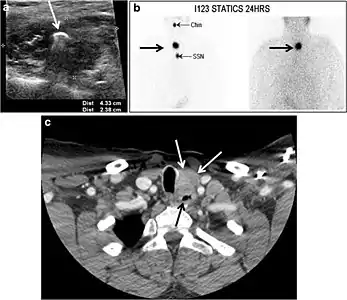

Intra-thyroid parathyroid adenoma

Parathyroid adenoma (PA) is the most common cause of primary hyperparathyroidism. Ectopic parathyroid adenoma is rare. The third and fourth pharyngeal pouches represent the embryological origin of the parathyroid tissues, and ectopic parathyroid adenoma can ultimately develop anywhere along their migration course. In a large retrospective study of patients with primary hyperparathyroidism, PA was detected in the intra-thyroid location in 0.7% of cases. In another retrospective analysis of 202 patients with ectopic PA, the intra-thyroidal location was found in 18% of the cases. Intra-thyroid parathyroid adenomas mimic thyroid nodules in CT scans and may even show uptake on a thyroid iodine scan. Correlation with laboratory workup, including measurement of serum parathyroid hormone and calcium level, is required. In addition, the evaluating radiologist should search for radiological manifestations of hyperparathyroidism, such as osteopenia, bone resorption, and brown tumours (Fig. 22).[1]

Fig. 22. A 26-year-old male patient with elevated serum parathyroid hormones and calcium secondary to intra-thyroid parathyroid adenoma. a, b Enhanced axial and coronal CT scan of the neck demonstrate a well-defined hypodense right thyroid nodule (white arrows). c Bone window coronal CT scan shows lytic expansile lesions at the right mandible and left frontal bone (white arrows). d Transverse colour Doppler ultrasound of the neck demonstrates a well-defined, heterogonous, predominantly hypoechoic right thyroid nodule measuring 2.7 cm, with mild increased vascularity and no internal micro-calcifications (white arrow). e, f Delayed anterior planar and fused SPECT/CT parathyroid Sestamibi scan at 2 hours demonstrate persistent focal activity in the right thyroid lobe (white arrows). Note the scattered mandibular/maxillary uptakes in planar image representing the known brown tumours.[1]

In the case of inconclusive Tc99m Sestamibi and neck US imaging, FNA biopsy with FNA-iPTH (intact parathyroid hormone) measurement can provide simultaneous biochemical and cytological evidence. Elevated FNA-iPTH measurement, as compared to serum iPTH, is considered positive and diagnostic of parathyroid adenoma.[1]